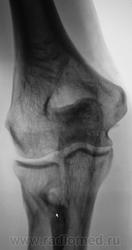

Представленное ниже (желтые стрелки), можно рассматривать как вариант развития (нормы), или как-то по- другому?

на мой взгляд что-то есть. вздутие прокимальной трети лучевой кости с истончением кортикального слоя, остеопороз. какая то костная киста. нужна другая сторона, клиника. недалеко до патологического перелома.

Кист не видно, вероятно такая глубокая шейка луча...

А не было ли тут перелома шейки лучевой кости?

Я думаю, что это, все-таки, вариант развития. Посмотрите вот здесь http://radiographia.ru/node/1393 , я там выкладывала два подобных случая у детей, тоже мне тогда не понятных. Пришла к выводу, что это вариант развития.

Может все таки что та давит со стороны локтевой кости, давит давно и долго - вот тогда это будет аррозия - атрофия от давления...Как Вы думаете?

Вряд ли так может давить, это не похоже на атрофию от давления.

Да, высказывались. Но ничего того, что могло вызвать атрофию от давления, выявлено не было, и жалоб никаких нет.